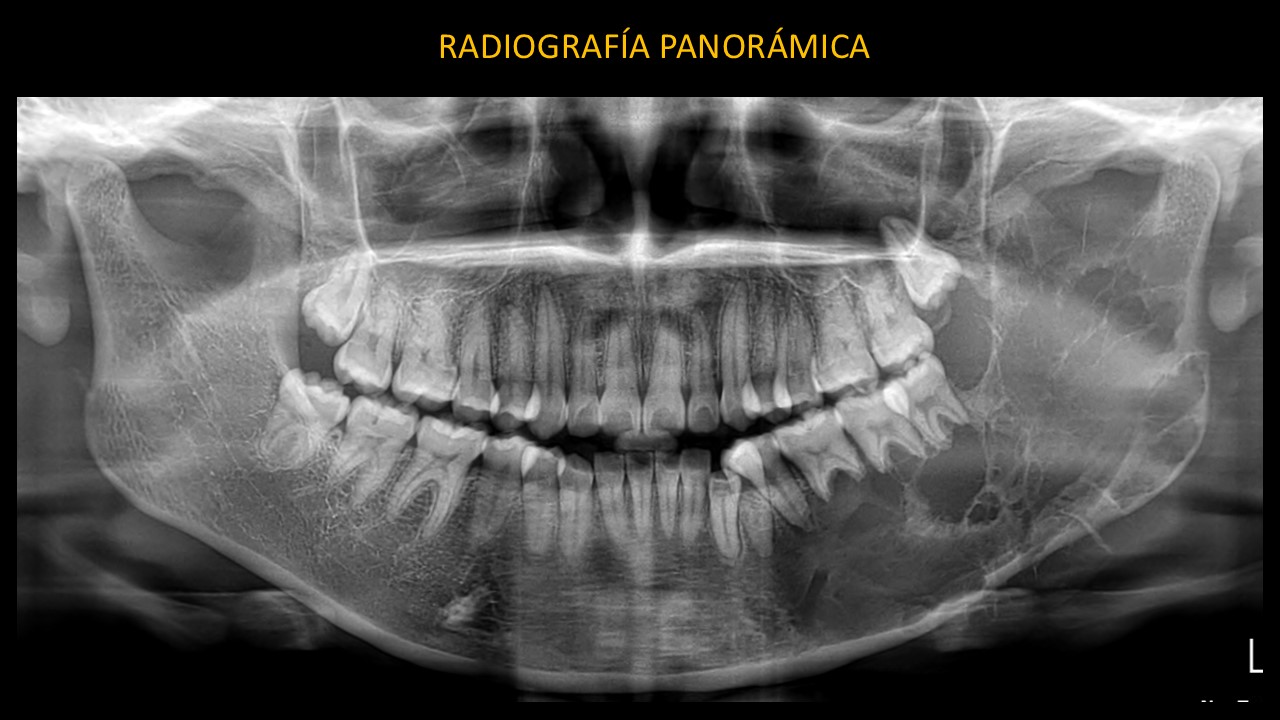

Figura 1

En la radiografía panorámica (Figura 1) se evidencia una imagen mixta en cuerpo mandibular, ángulo, rama ascendente y apófisis coronoides del lado izquierdo, de límites parcialmente definidos, forma irregular, que se extiende en sentido céfalo caudal desde la apófisis coronoides hasta la basal mandibular y en sentido mesio distal desde apical de la pieza 33 hasta el borde posterior de la rama mandibular.